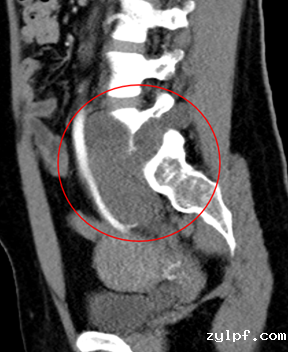

患者21岁女性,因左下腹隐痛2月,检查发现左腰骶椎前占位4天来诊。入院后进一步完善影像学检查提示左侧L5/S1椎间孔及椎体前后方占位。病灶钻缝生长,延伸至椎管内,再沿L5左侧横突孔向后伸至脊柱旁,横突孔增宽增大,骨质变薄,邻近肠管、左侧髂总血管稍推压移位。穿刺活检结果提示神经鞘瘤。

图片 7.png

因肿瘤成哑铃状跨越椎体前后方,手术需行前后联合入路,前方入路需面对髂血管、输尿管等重要结构,后方则有脆弱的脊髓及神经根,对手术技巧要求极高,并且需要手术医生掌握大量的解剖学知识。经过充分的术前准备及术中的精细操作,完整切除肿瘤并重建脊柱稳定性。术后患者下肢功能未受影响,复查腰椎正位片示内固定稳定在位,CT示肿瘤已完整切除。